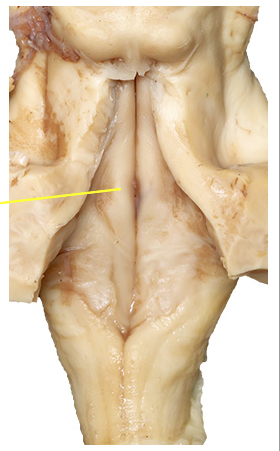

what is the yellow line point at?

Facial colliculus

what is the yellow line pointing at? what does it signify?

Medullary striae - pontocerebellar fibres that devide the floor fo the 4th ventricle into pontine and medullary